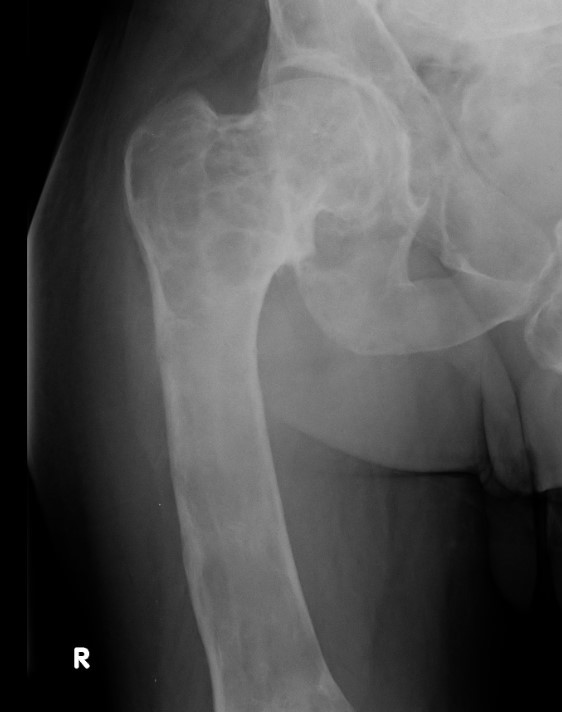

X-ray

Intramedullary lucent diaphyseal lesion with 'ground glass appearance'

- thinned, slightly bulged cortex

- ± endosteal scalloping

- may have angular deformity / bowing

Coxa vara and Shepherd's Crook deformity of proximal femur

- Shepherd's Crook - anterior bowing of femur

- secondary leg length discrepancy

- pain, difficulty walking